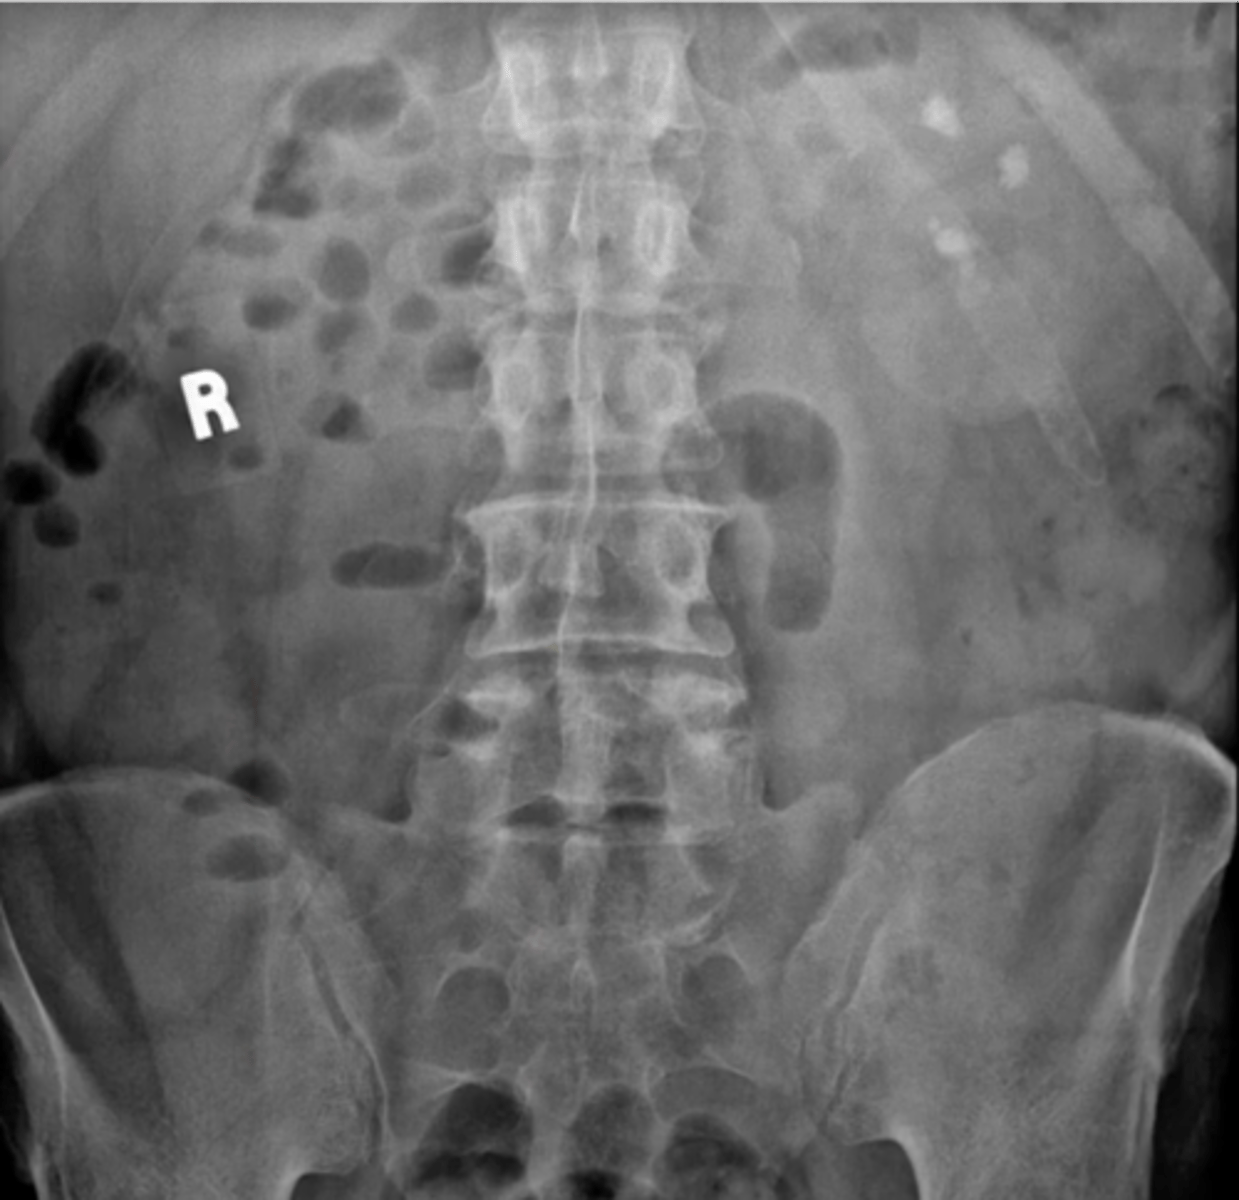

Kidney stones

Kidney stones (pic 2)

kidney stones (pic 3)

renal calculi (and ureteric stone)